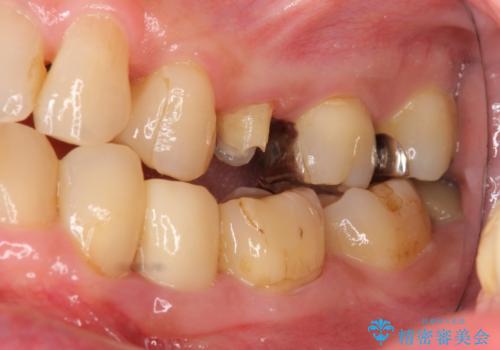

- 左上5番の根の治療途中で転院希望で来院。

割れているために抜かないといけないと説明されたとのことでした。

特に割れている所見はなかったため、根の治療から被せ物まで治療を行いました。

奥の銀歯のやりかえも希望されたため、セラミッククラウン、インレーにする治療をしています。